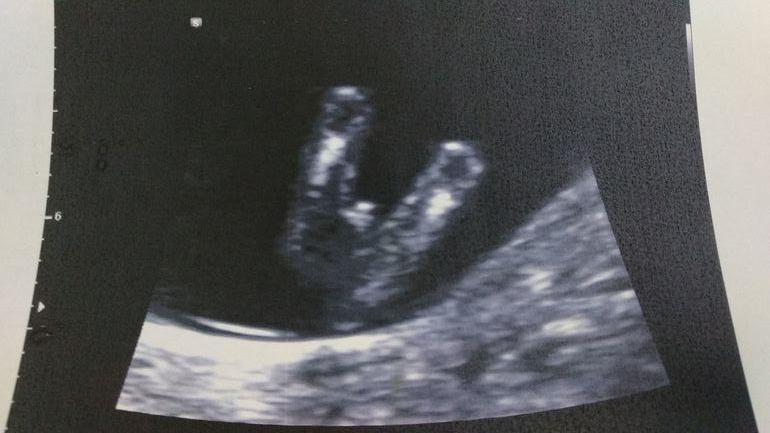

Мне кажется у меня просто пацаны такие с письками и без комплексов. Но врач в 12 и 3 сказал безапелляционно что это мужик )))

(Нипс подтвердил, хотя по фото как бэ нет сомнений)